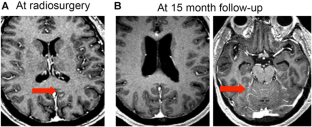

Leptomeningeal disease (LMD) is well described in patients with brain metastases, presenting symptomatically in approximately 5% of patients. Conventionally, the presence of LMD is an indication for whole brain radiation therapy (WBRT) and not suitable for stereotactic radiosurgery (SRS). The purpose of the study was to evaluate the local control and overall survival of patients who underwent SRS to focal LMD. We reviewed our prospective registry and identified 32 brain metastases patients with LMD, from a total of 465 patients who underwent SRS between 2013 and 2015. Focal LMD was targeted with SRS in 16 patients. The median imaging follow-up time was 7 months. The median volume of LMD was 372 mm3 and the median margin dose was 16 Gy. Five patients underwent prior WBRT. Histology included non-small cell lung (8), breast (5), melanoma (1), gastrointestinal (1) and ovarian cancer (1). Follow-up MR imaging was available for 14 patients. LMD was stable in 5 and partially regressed in 8 patients at follow-up. One patient had progression of LMD with hemorrhage 5 months after SRS. Seven patients developed distant LMD at a median time of 7 months. The median actuarial overall survival from SRS for LMD was 10.0 months. The 6-month and 1-year actuarial overall survival was 60% and 26% respectively. Six patients underwent WBRT after SRS for focal LMD at a median time of 6 months. Overall, focal LMD may be may be treated successfully with radiosurgery, potentially delaying WBRT in some patients.